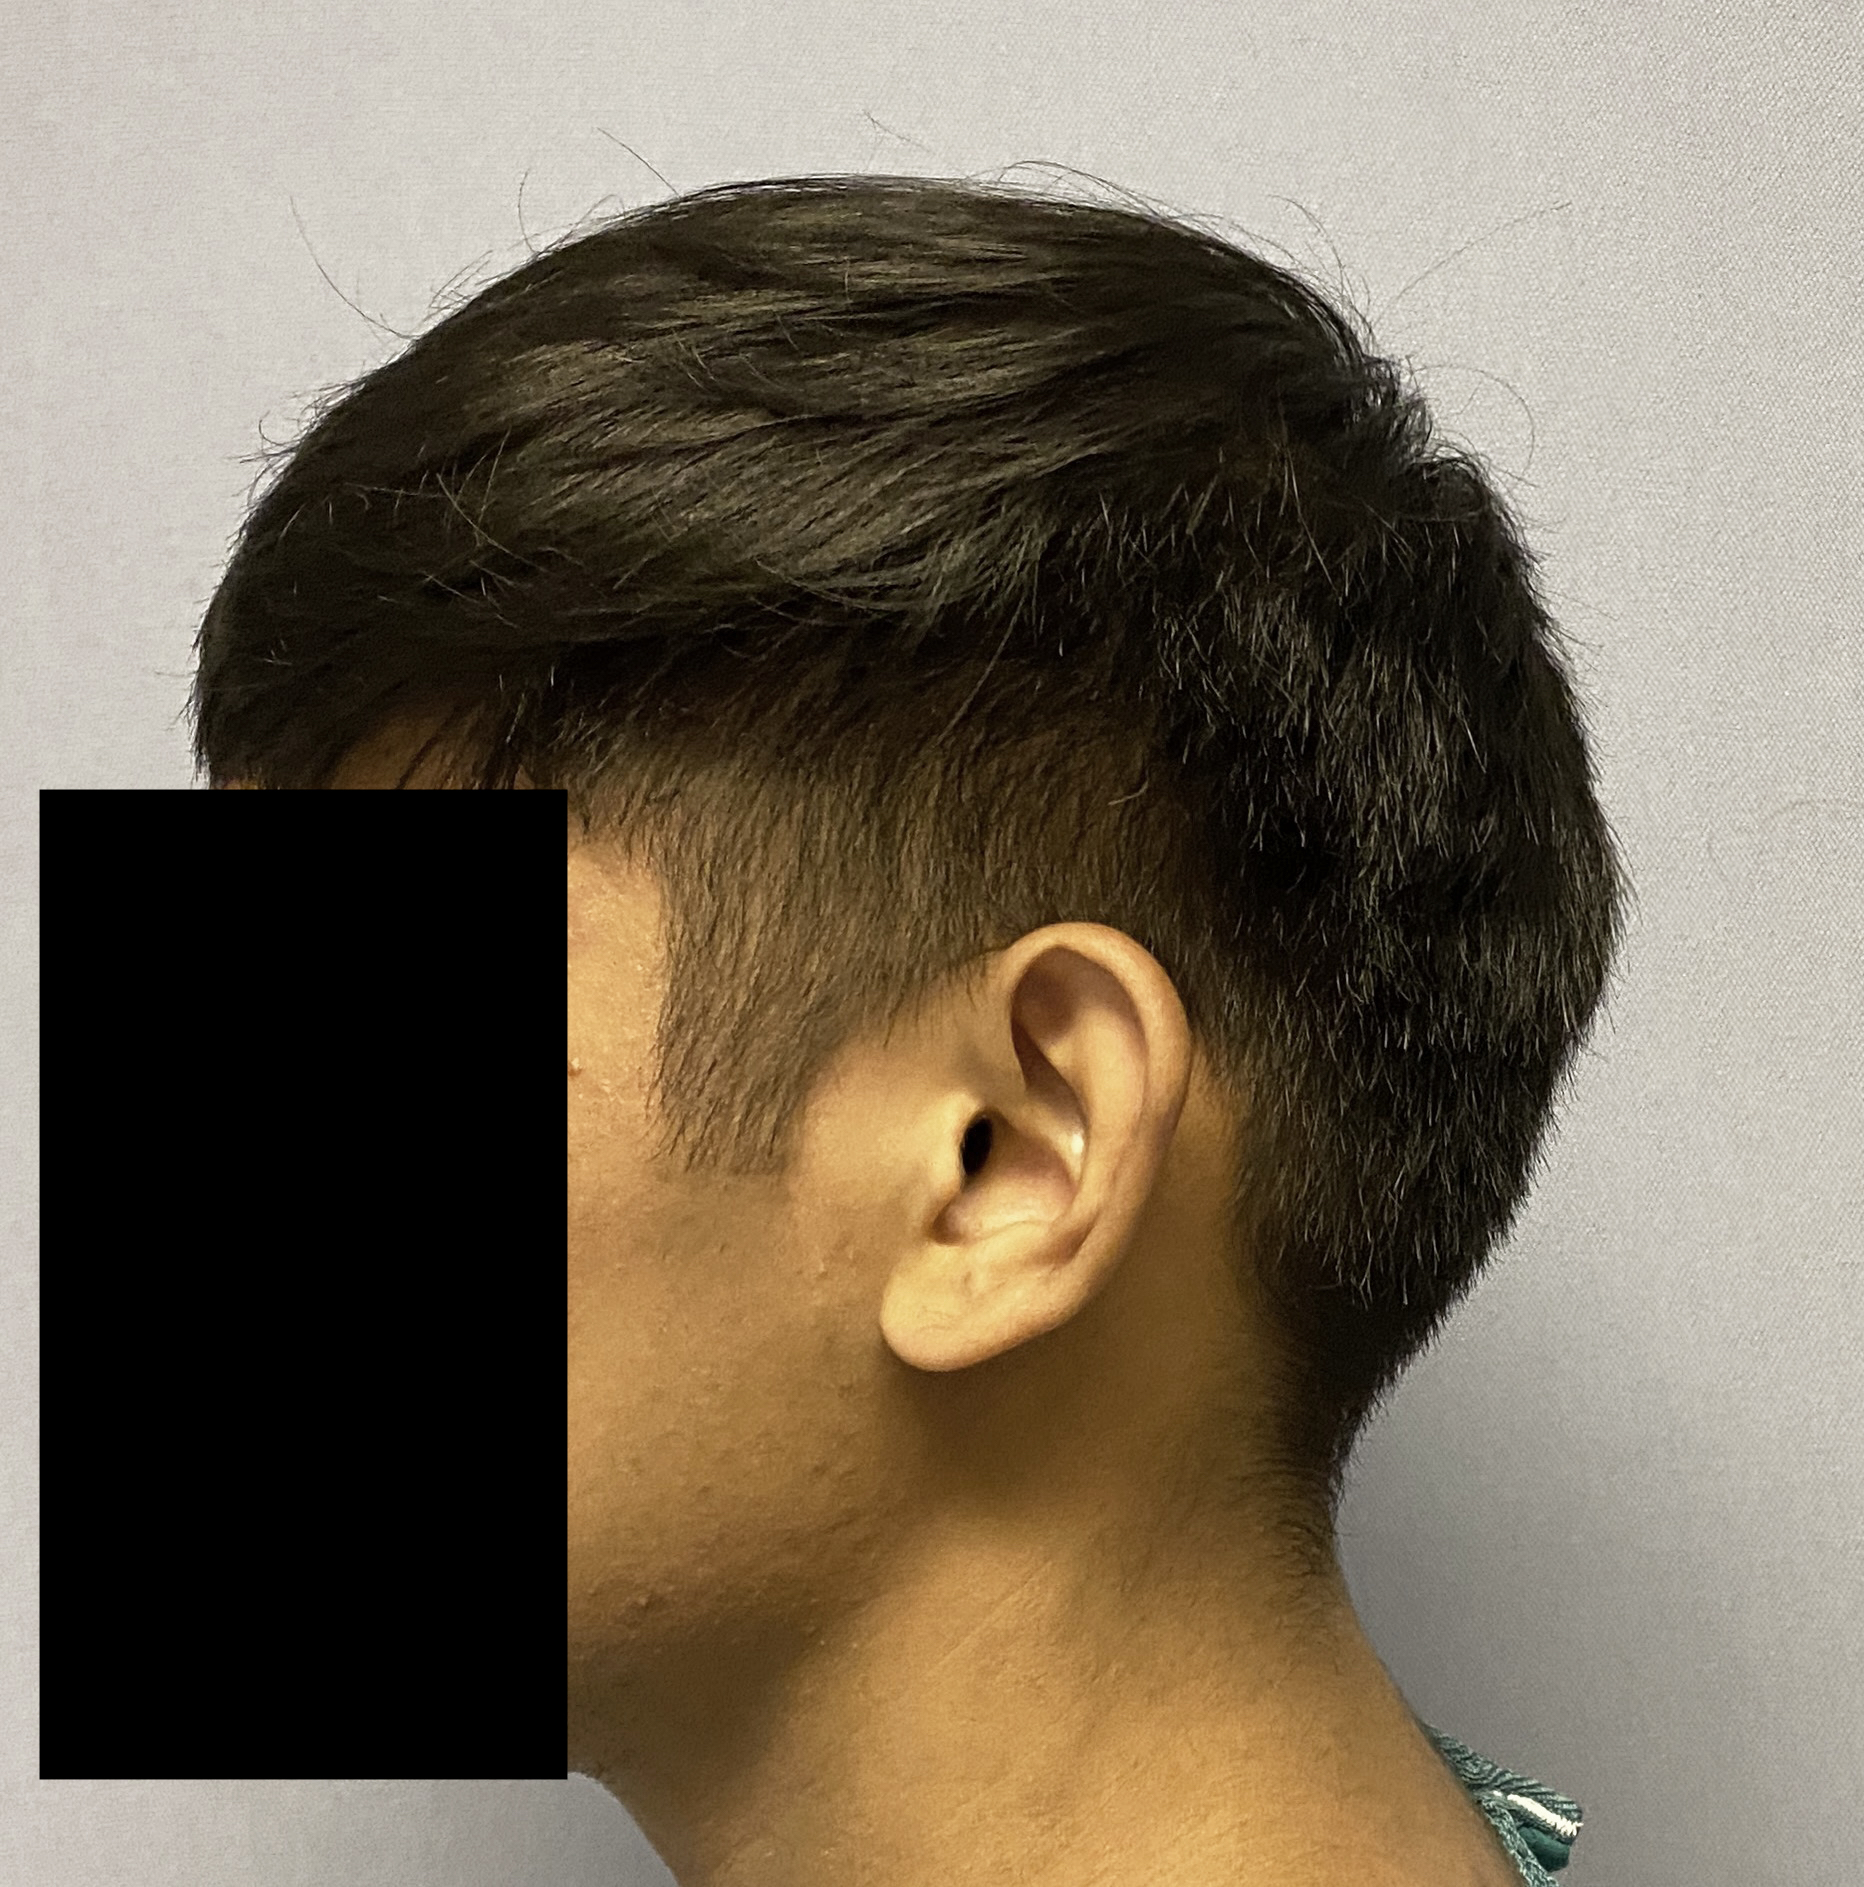

Young male seeking reduction of his convex sides of his head.

Head width reduction by posterior temporal muscle reduction through hidden postauricular incisions behind the ears.